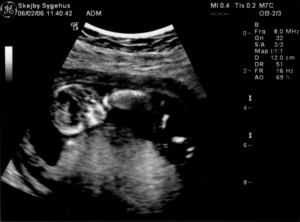

Ultralydsskanning den 6. februar 2006

Vi har i dag været på Skejby Sygehus og få foretaget en ultralydsskanning af baby. Der var kun én (pyh)! Baby blev målt og gennemset for eventuelle misdannelser. Der blev set efter at kraniet var begyndt at blive dannet og at der var to hjernehalvdele. Vi så to arme og to ben og der var fem fingre på den hånd vi så. Vi så også hjertet slå. Til sidst blev der blev målt bredden på nakkenfolden for at vurdere risikoen for mongolisme. Konklussionen var, at alt var som det skulle være. Du kan se de billeder vi fik fra skanningen herunder.